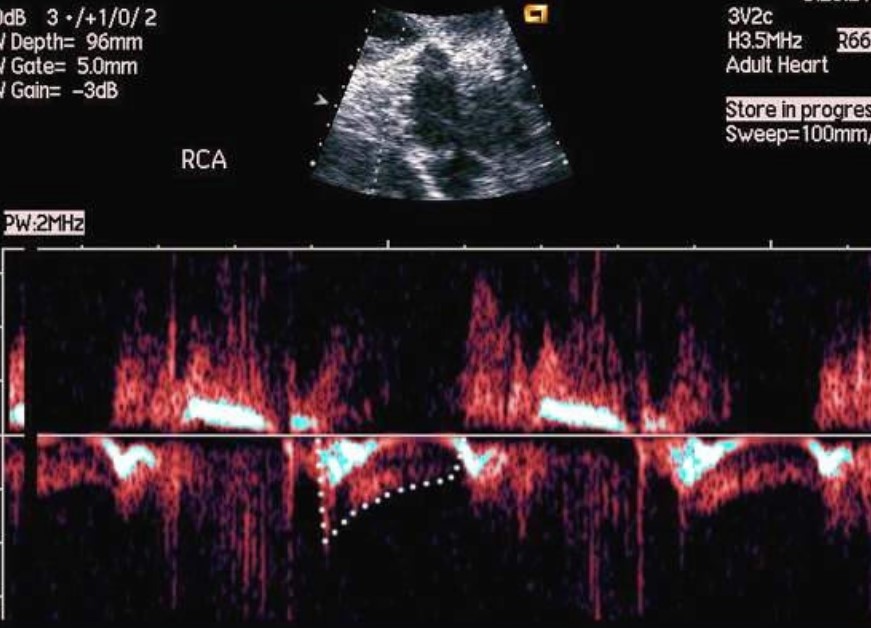

17 lis 2025 USG Doppler tętnic nerkowych – kiedy za wysokie ciśnienie „zaczyna się w nerkach”? Czytaj więcej